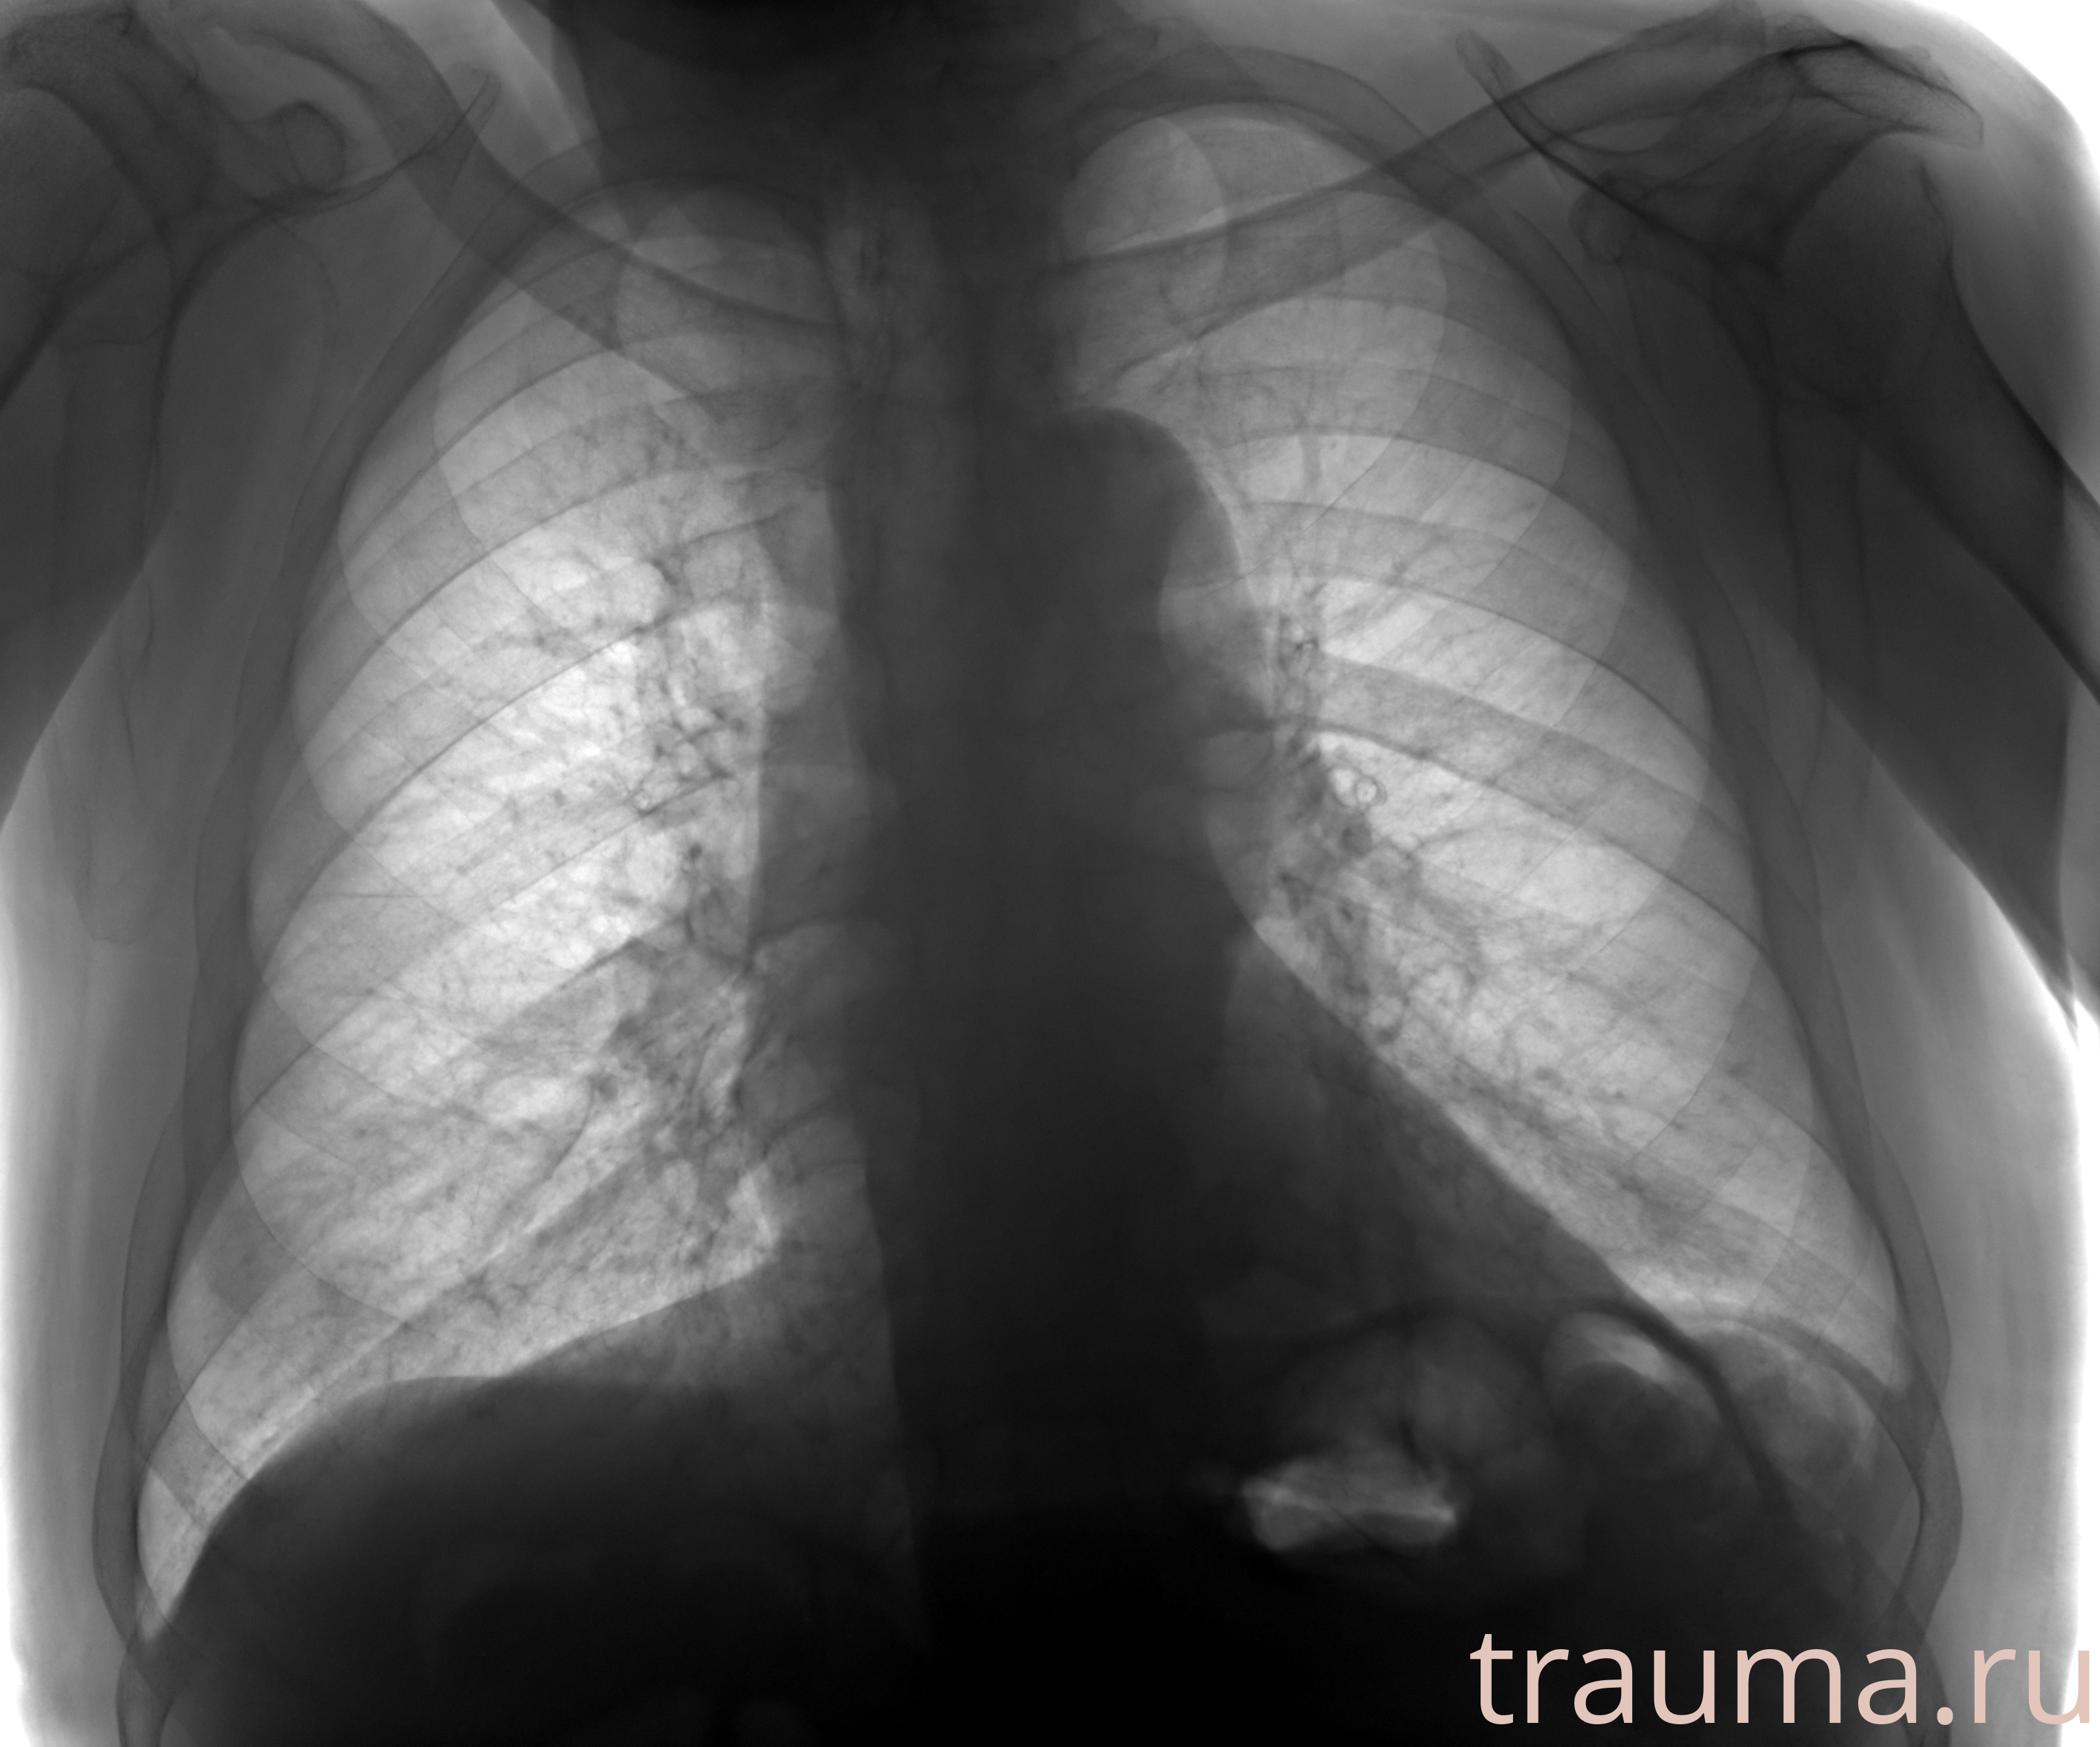

Рентген на дому: по вашему адресу приезжает врач-рентгенолог, травматолог-ортопед с мобильным рентгеновским аппаратом, проводит диагностику травмы или заболевания, делает необходимые рентгенограммы, дает рекомендации по дальнейшему лечению. Получить качественные снимки в домашних условиях возможно благодаря уникальной методике, разработанной МосРентген Центром для института  Склифосовского